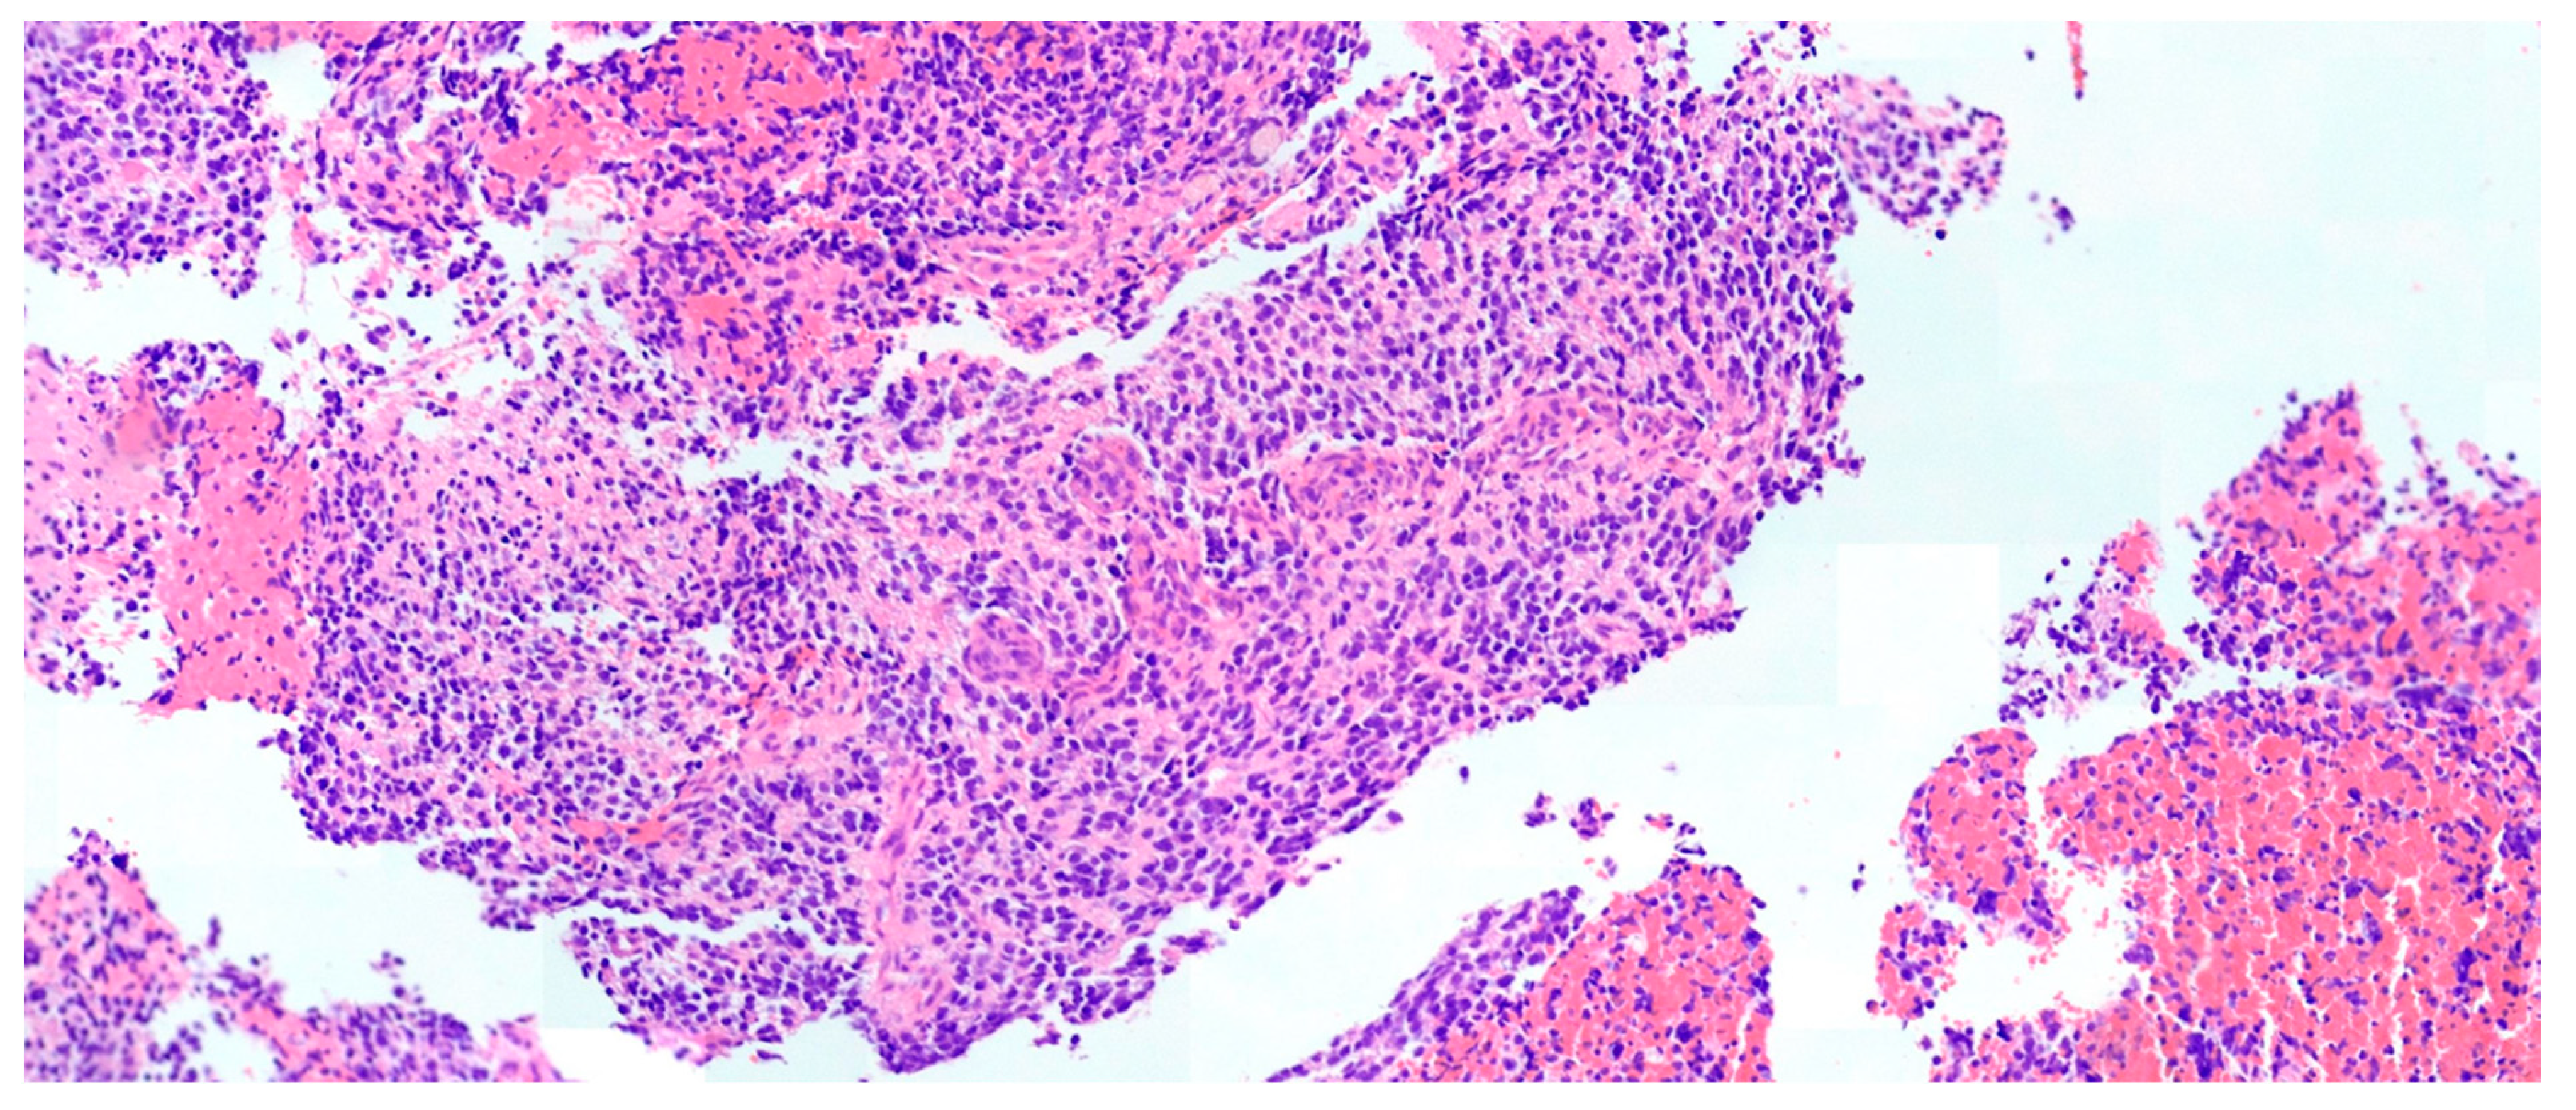

Case Report